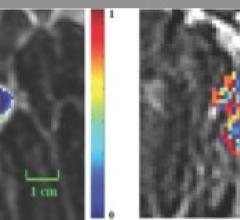

Prostate cancer is the leading cancer among men, second only to skin cancer. With surgical removal at the frontline of defense, oncologists are considering prostate-specific molecular imaging at the point of initial biopsy and pre-operative planning to root out the full extent of disease, researchers revealed at the 2016 Annual Meeting of the Society of Nuclear Medicine and Molecular Imaging (SNMMI).